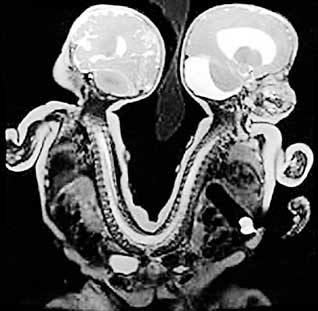

மருத்துவத் துறையில் வியக்கத்தகு சாதனைகளை படைப்பதில், தங்களை மிஞ்ச வேறு யாரும் இல்லை என்பதை, மீண்டும் ஒரு முறை நிரூபித்து இருக்கின்றனர், அமெரிக்க டாக்டர்கள். அமெரிக்காவின் மெம்பிஸ் என்ற பகுதியைச் சேர்ந்த ஒரு பெண்ணுக்கு, சமீபத்தில், இரட்டை குழந்தைகள் பிறந்தன. துரதிர்ஷ்டவசமாக, இந்த இரண்டு குழந்தைகளும், முதுகு ஒட்டி பிறந்தன. அதாவது, முதுகெலும்பின் மேல் பகுதியில் துவங்கி, இடுப்பு எலும்பு வரை, இரண்டு குழந்தைகளின் முதுகும் ஒட்டி இருந்தது.

ஆனாலும், அங்குள்ள பிரபல குழந்தைகள் நல மருத்துவமனை டாக்டர்கள், 13 நேரம் போராடி, அறுவைச் சிகிச்சை செய்து, இரண்டு குழந்தைகளையும், வெற்றிகரமாக பிரித்தெடுத்தனர். தற்போது, இரண்டு குழந்தைகளும், நலமுடன் உள்ளதாக, குழந்தைகளின் பெற்றோர் ஆனந்த கண்ணீர் வடிக்கின்றனர்.

டாக்டர்கள் கூறுகையில், 'பொதுவாக, ஒரு லட்சம் குழந்தைகள் பிறந்தால், அதில், ஒரு குழந்தை தான், இவ்வாறு முதுகெலும்பு ஒட்டிப் பிறக்கும். அதிலும், பெண் குழந்தைகள் தான், இவ்வாறு அதிகம் பிறக்கும். இவ்வாறு பிறக்கும் குழந்தைகளில், மூன்றில் ஒரு குழந்தை, ஒரு நாள் கூட, உயிருடன் இருக்காது. ஆனாலும், தற்போது மெம்பிசில் பிறந்துள்ள குழந்தைகள், நலமுடன் உள்ளது, எங்களுக்கு மகிழ்ச்சியை ஏற்படுத்தியுள்ளது. மருத்துவத் துறையில், இது ஒரு மகத்தான சாதனை...' என, பெருமிதப்படுகின்றனர்.